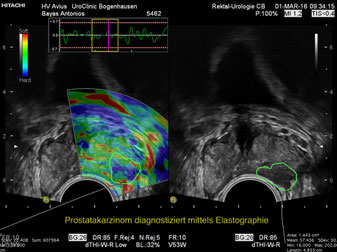

Real-time Tissue Elastography (RTE)

RTE ist ein neuartiges Diagnosewerkzeug für die Beurteilung und Darstellung der Gewebeelastizität in Echtfarbe. Wenn eine diagnostische Biopsie (Prostata) indiziert ist, ermöglicht RTE eine präzisere Lokalisierung und ein genaueres Targeting von Läsionen als konventionelle Techniken.

Ultraschall - Elastographie